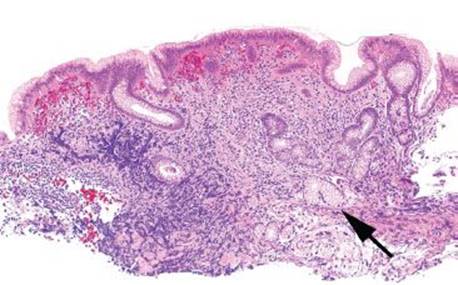

Figure 2.99 Chronic gastritis pattern, antral pyloric gland atrophy, EMAG. Antral atrophy has poor interobserver concordance and can be difficult to evaluate; however, this example shows a marked reduction in the pyloric glands (bracket) as compared to the full thickness of the biopsy. Isolated antral atrophy is commonly associated with Helicobacter. Not the top-heavy superficial plasmacytic infiltrate in this case.